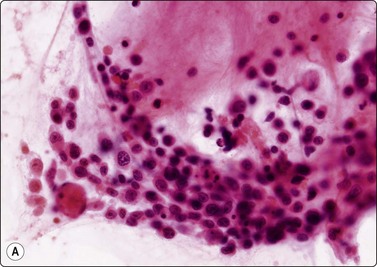

image image

Fig. 8.4 Neutrophil rosette

(A) Clump of neutrophils (H&E, HP oil); (B) Fine branching filaments of Nocardia (Methemamine silver, HP oil).

A high polymorph content is usually present in the inflammatory reaction to fungi. A search for a granulomatous component and fungal organisms is mandatory if acute inflammatory material is obtained. With infection by filamentous organisms, e.g. Nocardia, the organisms may be identified in the center of distinctive, cohesive neutrophil clusters or rosettes after silver impregnation; this clustering should be a clue to search for such an infection (Fig. 8.4). Similar appearances may also be be seen in streptococcal infection.